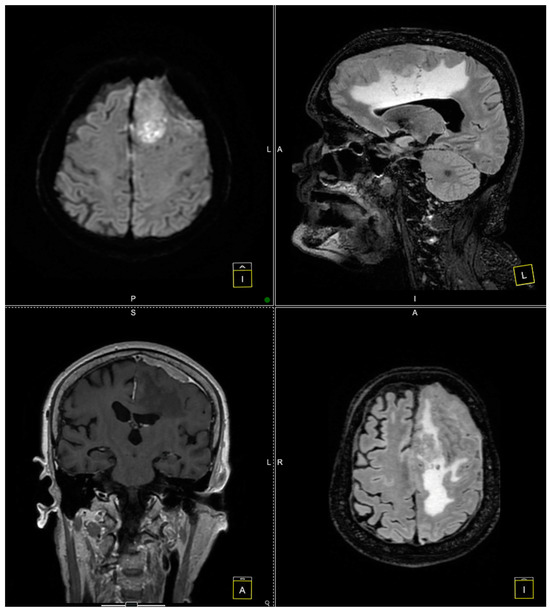

Further evaluation with contrast-enhanced MRI confirmed the presence of a tumoral mass, which was isointense with brain parenchyma on T1-weighted images and moderately hyperintense on T2-weighted images, with intense and homogeneous enhancement following contrast administration. Notable peritumoral cerebral edema was observed, extending to the interhemispheric region and the corpus callosum. The lesion appeared suggestive of a meningioma measuring 4 × 6 cm. The remainder of the brain appeared normal on T1- and T2-weighted sequences, as well as after contrast administration (Figure 1 and Figure 2).

Figure 1. Preoperative MRI. The preoperative MRI scans display a large, convexity en plaque meningioma in the left frontoparietal region, extending toward the parasagittal area. The tumor exhibits homogenous enhancement on T2-weighted images, indicating a highly vascular lesion consistent with meningiomas. The tumor’s dimensions are approximately 4 × 6 cm, and it infiltrates the dura mater, extending deeply toward the paraventricular area. This infiltration reaches the superior sagittal sinus, posing challenges for surgical resection due to the involvement of this critical venous structure. The dashed frames indicate the area of interest, while the yellow lines mark intersecting planes across axial, sagittal, and coronal views, facilitating anatomical correlation and spatial orientation for surgical planning.

Figure 2. Preoperative MRI. The preoperative MRI scans illustrate a large, homogeneously enhancing convexity en plaque meningioma located in the left frontoparietal region. In these images, the tumor’s infiltration of the dura mater and partial involvement of the superior sagittal sinus are evident, posing additional complexity for surgical resection.